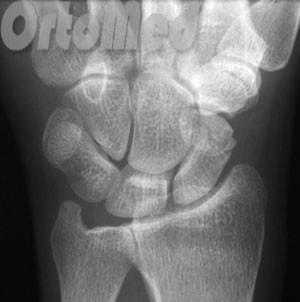

Функция пальцев полная. Сила кулачного схвата правой (доминантной) кисти — 22 кг, снижена почти в 2 раза по сравнению с нормой. Сила схвата левой кисти — 40 кг. Оценка по шкале ВАШ — 3 балла, по опроснику DASH — 21,16 балла. На рентгенограмме (рис. 5, а, б, в) и при компьютерной томографии выявлен ложный сустав ладьевидной кости (см. рис. 6, г). Рис. 6. Пациент К., 19 лет. Диагноз: ложный сустав ладьевидной кости правой кисти. а — рентгенограмма в прямой проекции; б — рентгенограмма в ¾; в — рентгенограмма в боковой проекции; г — компьютерная томография.

Начинать диагностику лучше всего с осмотра у врача, при подозрении на травму запястья делают рентгенограммы лучезапястного сустава. Важно сделать помимо стандартных прямой и боковой проекций еще и дополнительную косую, в которой лучше всего будет видна ладьевидная кость. Бывает так, что на первичных рентгенограммах перелом не выявляется. При сохранении симптоматики и отсутствии признаков костной травмы на рентгене следует повторить исследование через неделю или сделать компьютерную томографию (КТ) для уверенного подтверждения или исключения перелома.

Рентгенография. Это основной метод диагностики переломов ладьевидной кости, позволяющий в т.ч. оценить смещение фрагментов. Также рентгенография назначается для исключения любых других переломов.

В некоторых случаях перелом ладьевидной кости не виден на рентгенограмме. Если доктор подозревает такой перелом, но не видит его на рентгенограмме, он может порекомендовать вам иммобилизацию лучезапястного сустава в течение 2-3 недель с последующей повторной рентгенографией. Нередко по истечении этого периода перелом ладьевидной кости становится виден на рентгенограмме. В течение всего этого периода вы должны носить гипс или брейс и избегать тех видов физической активности, которые могут усугубить возможную проблему.